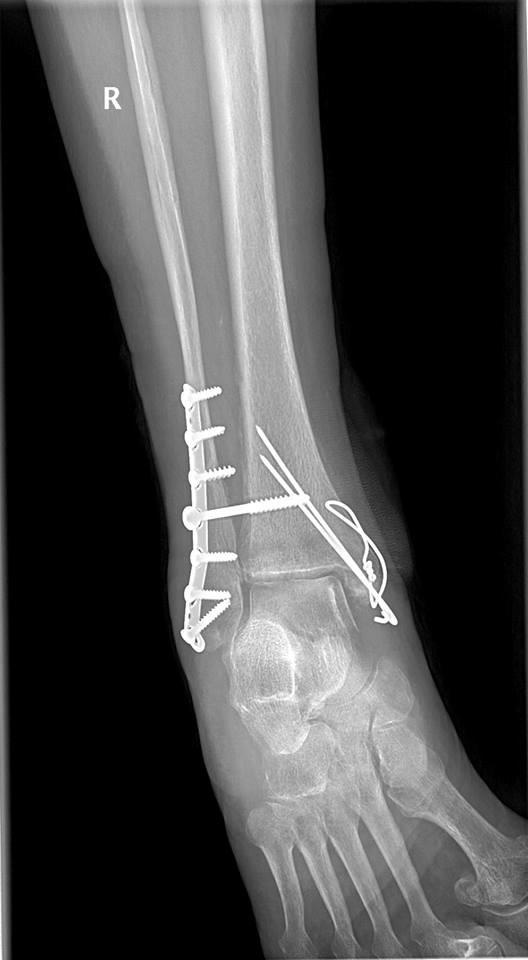

The injuries were severe—she needed surgery, and to this day, she has a metal rod inserted in one of her legs. The recovery was grueling. She spent weeks unable to walk, followed by months of intense physical therapy just to regain mobility. Even now, she still experiences occasional pain and stiffness.